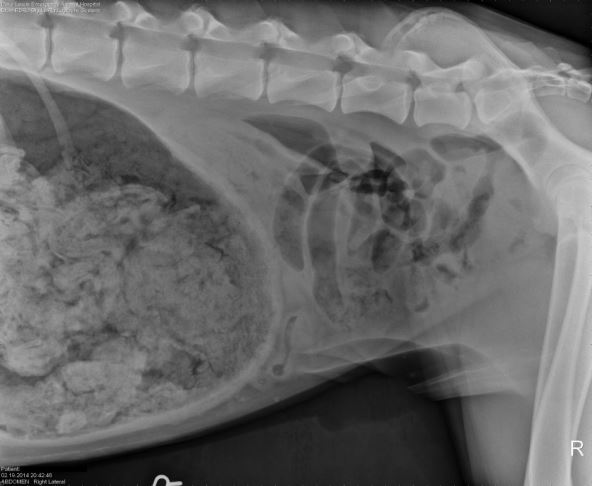

Ovog psa su čarape zanimale i ranije, ali nije bilo problema dok se nije razboleo i dok se pravi problem nije otkrio na rentgenskom snimku.

Eksperti u oblasti veterine bili su impresionirani toliko da je klinika odlučila da ljubitelja čarapa uključi u godišnje takmičenje pod nazivom "Šta to oni jedu?", gde je osvojio treću nagradu i 500 dolara!

Lekari su bili fascinirani rentgenskim snimkom Grejt Dena i poslali ga na takmičenje, na kom je osvojio treće mesto i 500 dolara